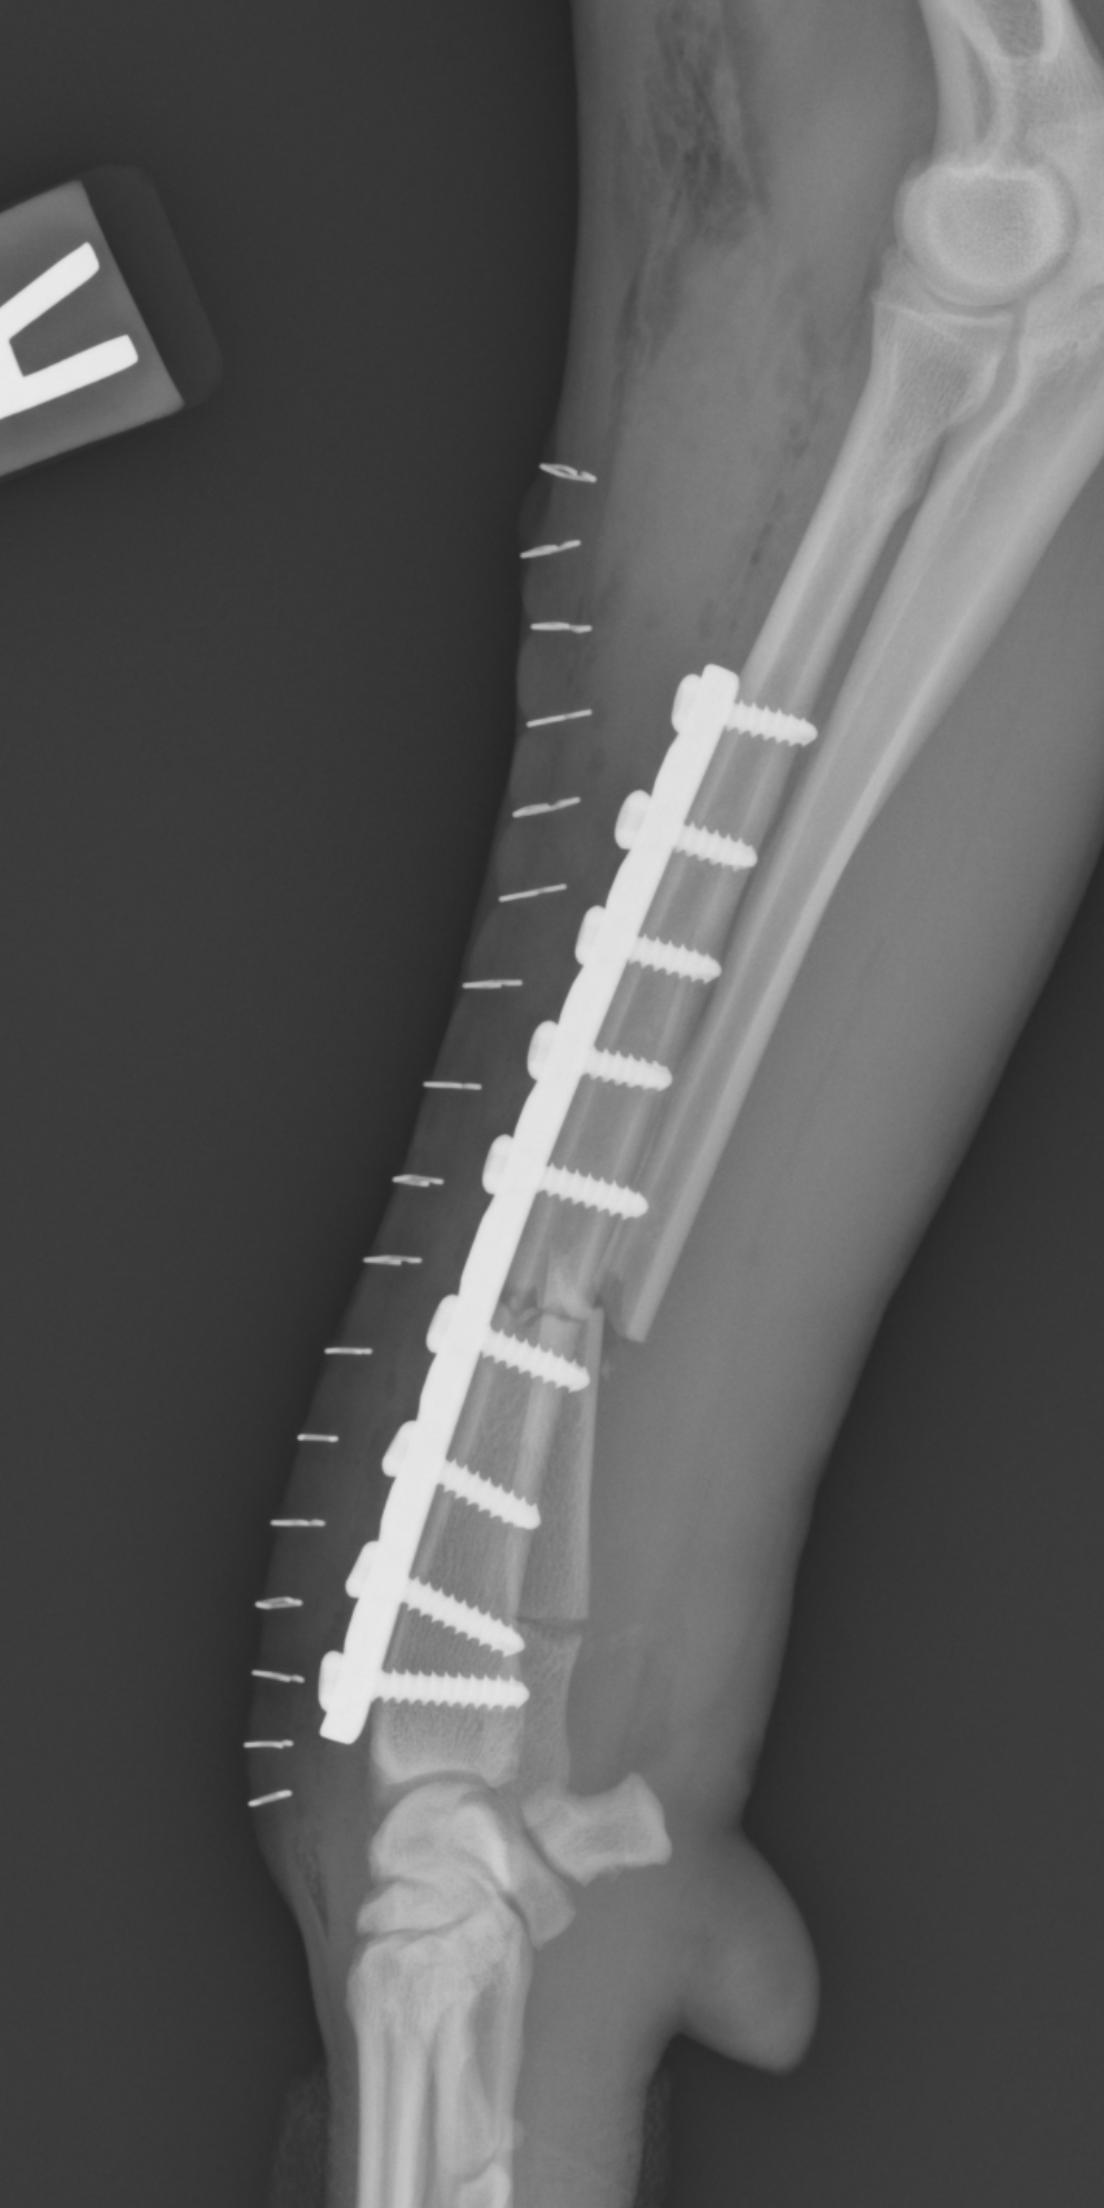

Patient with a Sliding Humeral Osteotomy (SHO).